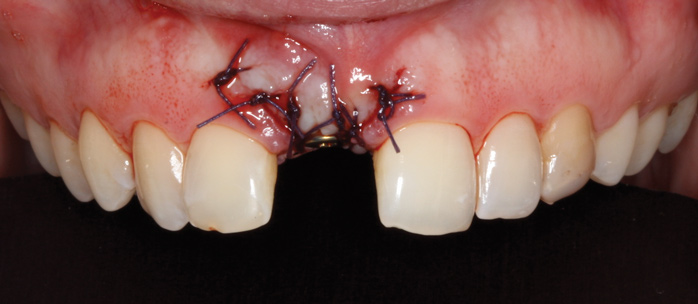

To place an implant without inducing recession, papillae-sparing incisions were created on the mesial and distal of the edentate area at site No. 8. Vertical incisions were made 1 mm away from adjacent teeth and connected with a mid-crestal incision (Figure 13). The extent of the vertical incisions was 3 mm buccally and lingually to expose the alveolar ridge. Horizontal and vertical bone regeneration was clinically confirmed (Figure 14). A 3.3-mm x 12-mm bone level tapered, narrow-connection implant (Straumann, straumann.com) was inserted, and it attained initial primary stability at 25 Ncm (Figure 15 and Figure 16). It was desired to have more than 1 mm of bone buccal and lingual to the implant so as to avoid bone resorption and recession. Then, 4-0 Vicryl single interrupted sutures were used to close the flap (Figure 17).

Fig 13. Papillae-sparing incisions connected mid-crestally.

Figure 13